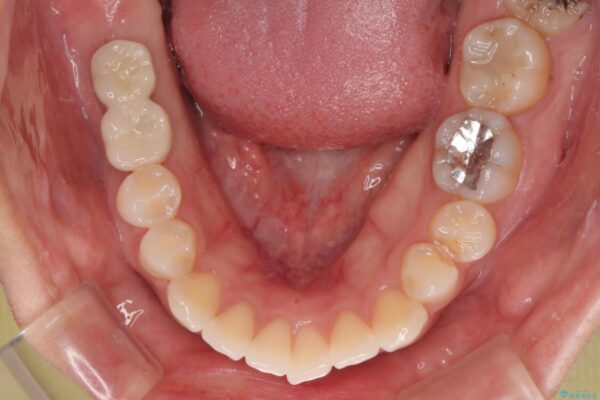

スペースが整った段階で、右下の第一大臼歯と第二大臼歯にインプラントを埋入。

その後、挺出していた右上第一大臼歯と第二大臼歯に装着されていた銀歯についても、審美性と適合性の向上を目的に、オールセラミッククラウンにやり替えました。

これにより、より自然で美しい見た目と、高い精度の咬合が得られています。

• 挺出歯を圧下してスペースを確保!目立たない部分矯正で下顎大臼歯にインプラント治療を実現 治療後画像